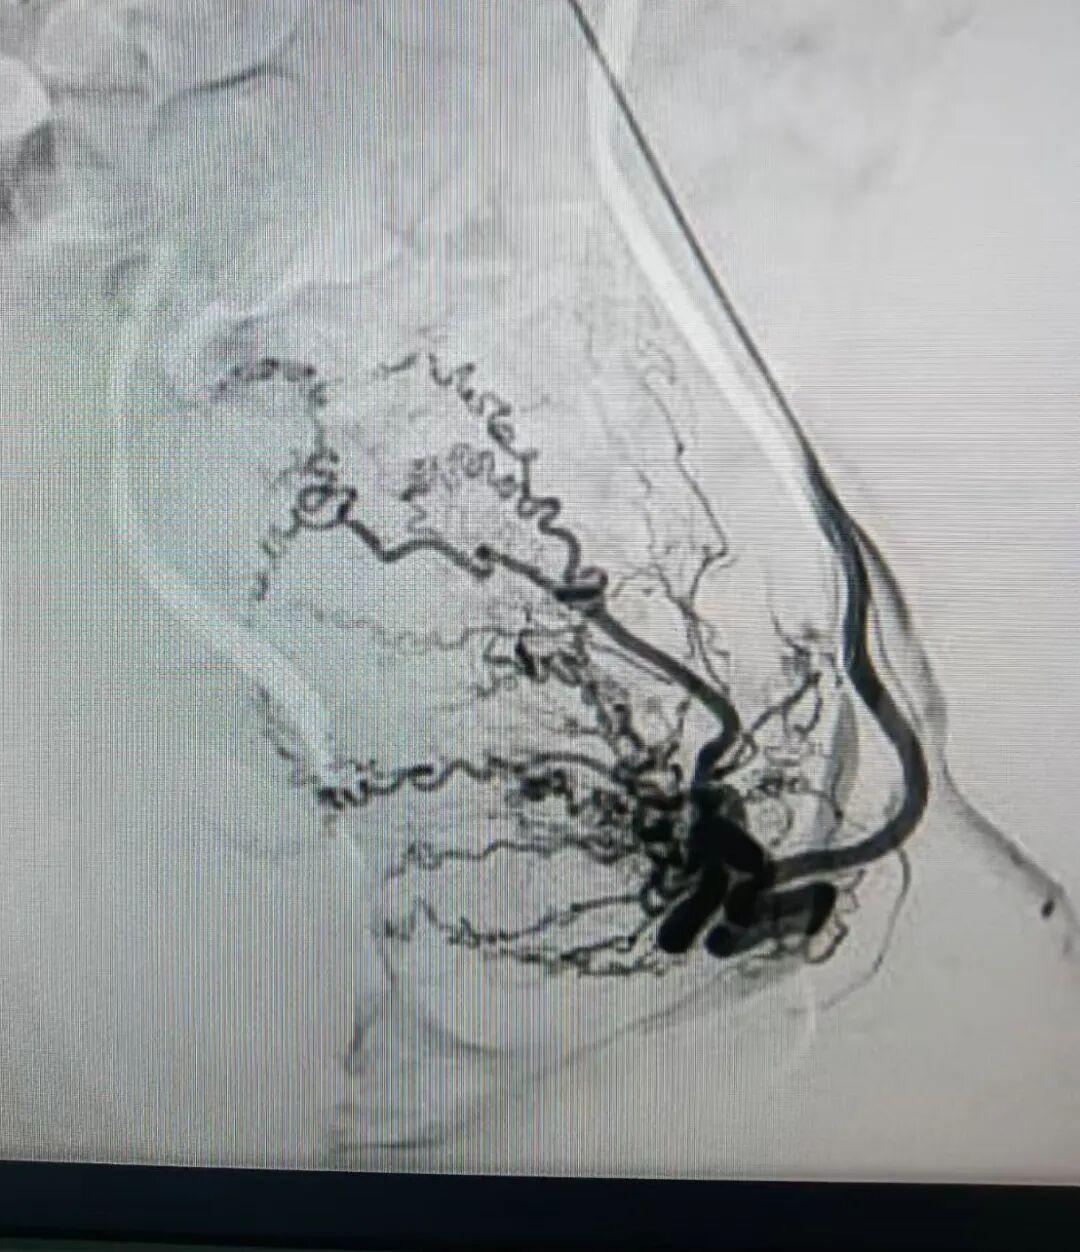

近日,洛阳白马医院介入科团队为患者成功施行了经远端桡动脉子宫动脉造影及栓塞术。手术仅在远端桡动脉处建立微小穿刺口,将导管精准送至子宫动脉。通过造影明确病灶的供血血管后,团队注入栓塞剂,阻断病灶血流,使异位内膜组织因缺血而逐渐萎缩,从而达到缓解疼痛、减少出血的目的。

子宫动脉栓塞术是一种血管性介入治疗方法,其原理是通过"堵血管"的方式,切断子宫腺肌病灶的血供。医生在患者一侧的大腿根部或手腕处用细针穿刺,仅留下一个微小的针眼,然后将导管在X光血管造影机的引导下,精准送达子宫动脉,注入栓塞颗粒,阻断病灶的血流供应。失去血供的病灶组织会逐渐缺血坏死、萎缩,从而缓解疼痛、减少月经量,达到治疗目的。

三、精准施治:高清DSA引导下的技术保障

洛阳白马医院作为一家二级非营利性综合医院,自1959年建院以来,始终秉持"以患者为中心"的服务理念。近年来,医院不断推进技术升级,已成功开展多项介入微创手术。医院配备了先进的飞利浦血管造影系统(DSA),能够提供高清的血管成像,使医生能够更精准地定位子宫动脉,确保手术的精确性和安全性。